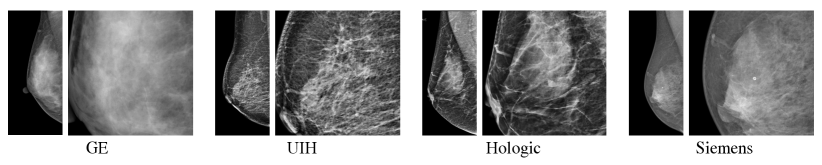

The advance of deep learning (DL) techniques have remarkably improved the computer-aided detection (CADe) of breast lesions in mammography. It has been shown in many studies [10, 12, 15] that the incorporation of DL-based CADe software in the reading workflow of mammography can effectively improve the detection accuracy. Promising DL-based CADe performance requires large and diverse training data. In particular, the inclusion of wide variety of vendors is very important to equip the DL-based CADe system with prominent generalization capability. As shown in Fig. 1, the styles of images from various vendors vary significantly. Accordingly, the generalization of DL-based CADe system may be limited if the data of each vendor are not sufficiently included in the training stage. However, the collection of large and diverse data with various vendors is very expensive and is impractical. Meanwhile, it is also well-known that there exists domain gap between datasets from various institutes. Therefore, a domain generalization method is needed to alleviate the demands of large and diverse data from various vendors for the DL-based CADe scheme.

In this paper, mammograms of four vendors, i.e., GE, United Imaging Healthcare(UIH), Hologic, and Siemens, denoted as A, B, C, and D, respectively, are involved. All the data of the four vendors were collected from Asian women. The data of vendors A, B and C are set as seen domains whereas the vendor D is treated as unseen domain. To evaluate the generalization capability of our method, we also involve the public dataset, INbreast [13], denoted as E as unseen dataset. In total, this study involves 28,700 mammograms, where 27,000 unannotated images are used for style transfer and contrastive learning. The remaining 1,700 annotated images are adopted for the training/validation/testing of the detection tasks. We conduct a preprocessing step to align various mammograms from A, B, C, D, and E into the same pixel spacing of 0.1 mm to facilitate the training of deep learning methods. For the assessment of detector, we adopt the mean average precision(mAP) metrics for the quantitative comparison.